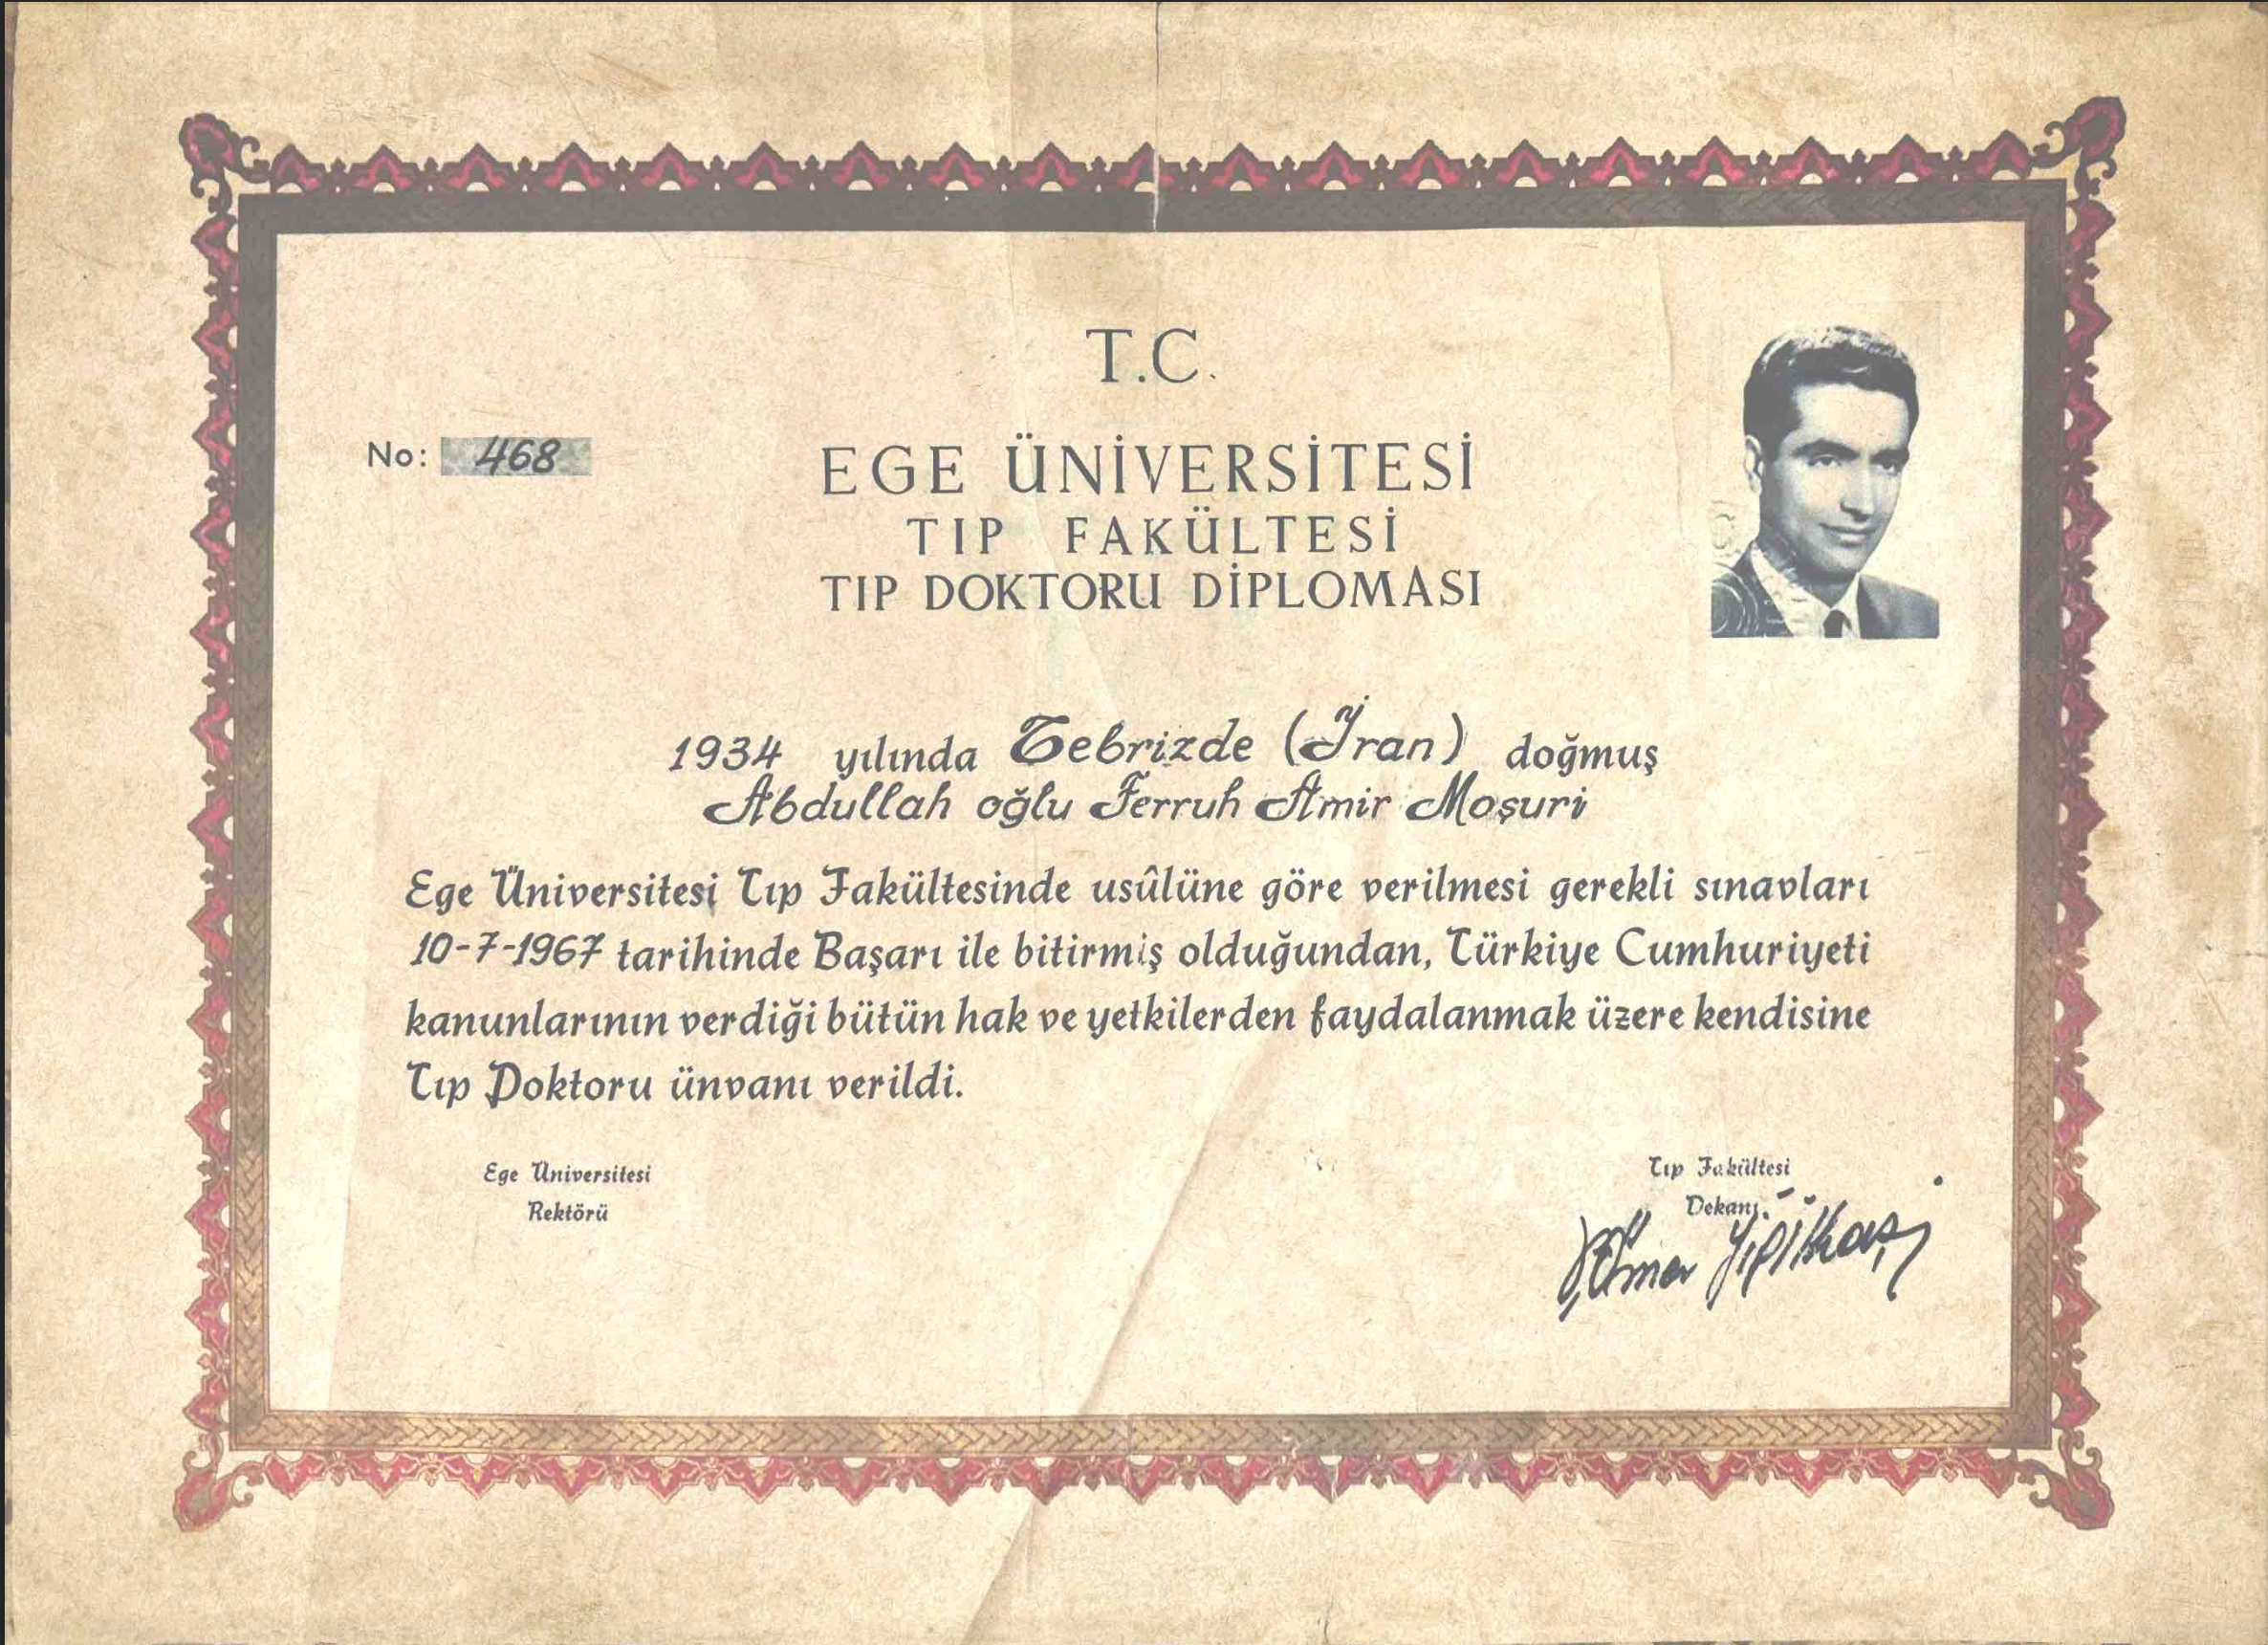

رویکرد درمانگاه مشیری

در درمانگاه مشیری:

- بیماریهای نادر و پنهان با دید سیستمی بررسی میشوند

- تشخیص زودهنگام ژنتیکی در اولویت است

- بیماران به مسیرهای درمانی نوین و علمی هدایت میشوند

- تمرکز بر پزشکی فردمحور و مبتنی بر شواهد روز دنیا است